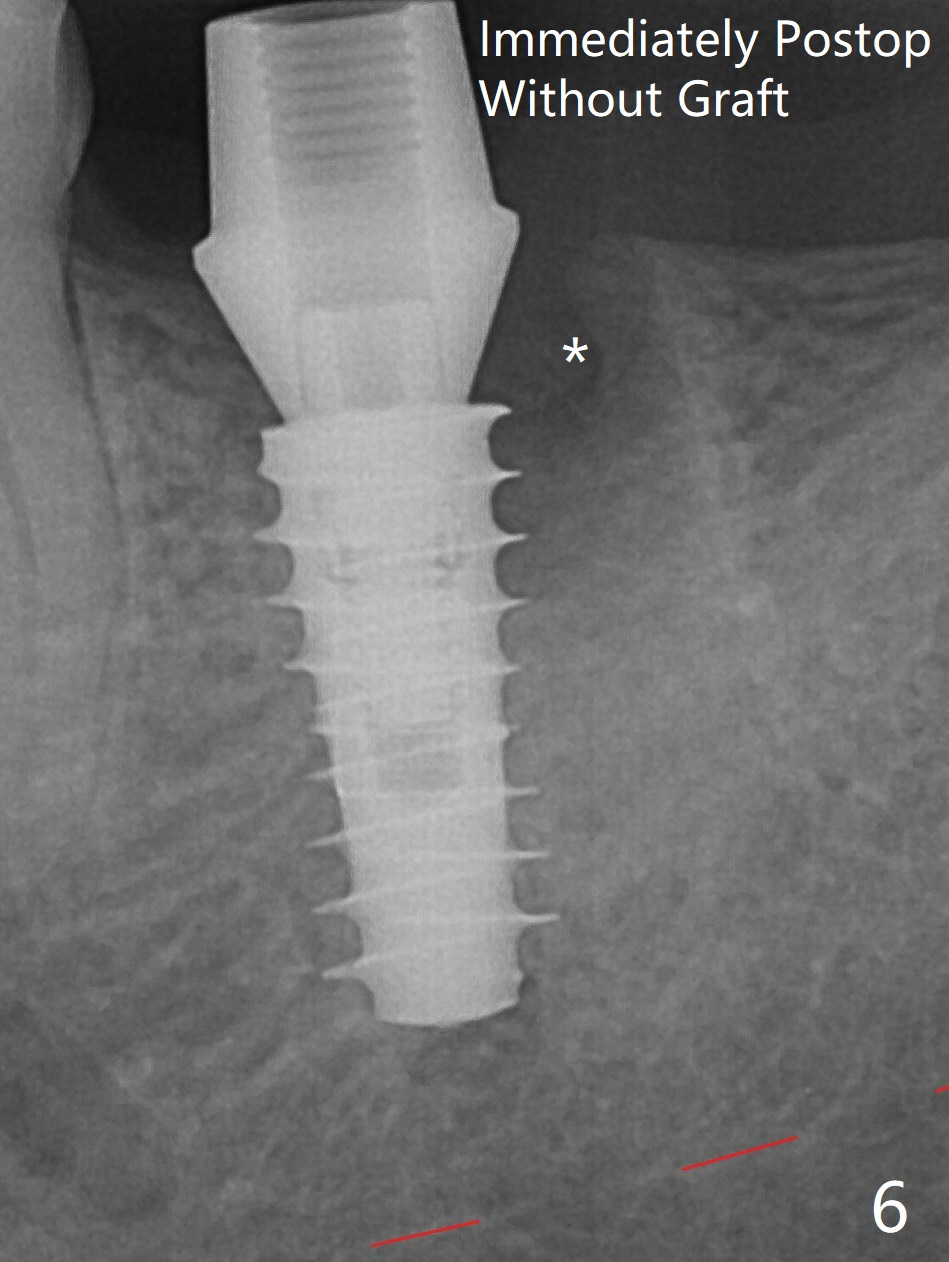

Following 4.8 mm MD, a 5x11 mm IBS implant is placed subcrestal circumferentially (Fig.6 with 50 Ncm). *: distal socket.